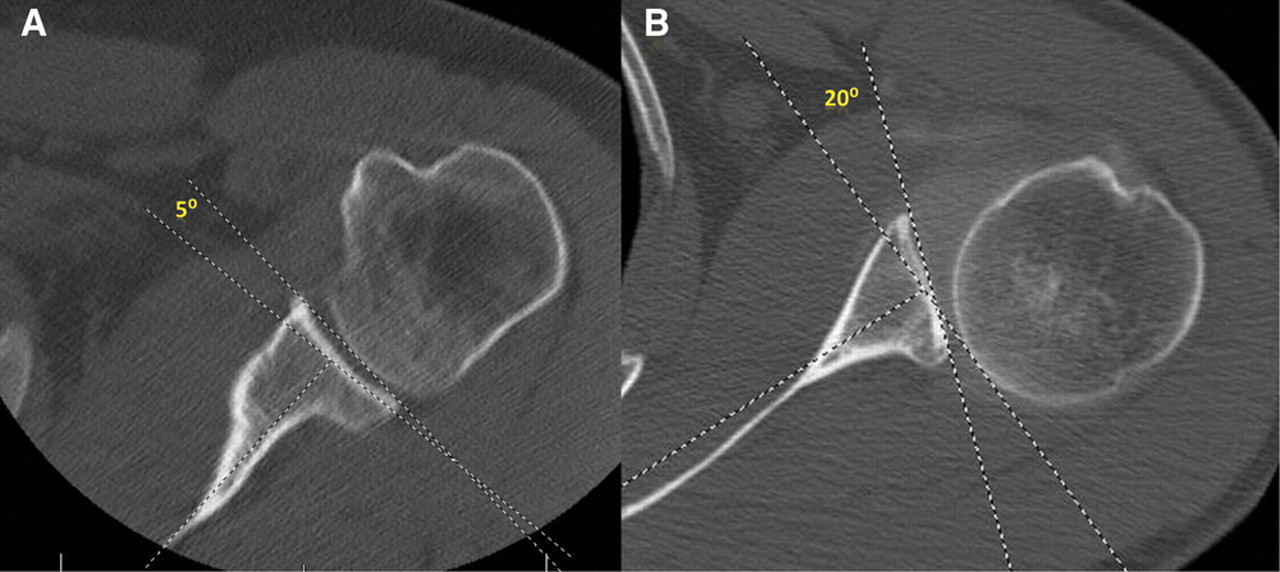

FTK Sports Medicine Bony Adaptation of the Shoulder in Baseball Pitchers Mlb Pitchers With Slap Tears Slap tears have variations that may lead to a stable or unstable type of lesion. The majority of slap tears don’t happen in one day and usually result from repetitive trauma inside the shoulder. Identified 24 mlb pitchers who underwent surgical management of slap tears and found a 62.5% rtp rate, with 86.7% of those who rtp returning to prior. Mlb Pitchers With Slap Tears.